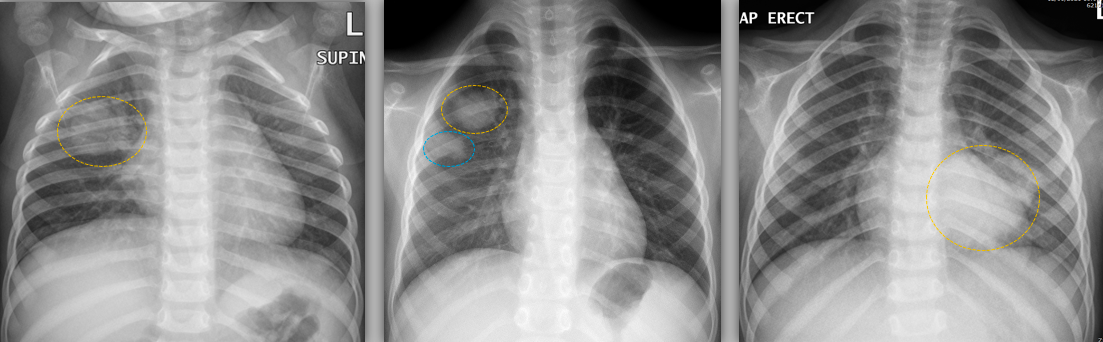

– Viêm phổi tròn nói chung thường gặp ở trẻ em và ít được báo cáo ở người lớn. Chẩn đoán cần được đặt ra ở bệnh nhân trẻ có hình ảnh lâm sàng viêm phổi điển hình.

– Viêm phổi tròn được do biểu hiện sớm của bệnh từ một ổ nhiễm trùng lan kiểu ly tâm, hoặc bằng cách đi qua các lỗ Kohn hoặc ống Lambert, hoặc bằng cách phá huỷ thành phế nang xung quanh. Một giả thuyết khác cho rằng viêm phổi tròn xảy ra ở trẻ em vì các lỗ Kohn chưa phát triển và không có ống Lambert làm hạn chế sự lan của vi sinh vật dẫn đến khối tròn, ổ thấy trên X quang và CT. Giả thuyết này cũng có thể giải thích tại sao viêm phổi tròn thường ít gặp hơn ở người lớn, có ống Lambert phát triển đầy đủ. Giai đoạn tạo hình tròn cũng có thể thấy khi viêm phổi lan toả thuyên giảm chậm, gợi ra quá trình bệnh lý thứ phát

– Nguyên nhân:

+ Trẻ em: Streptococcus pneumoniae, and less frequently Aspergillus spp., Legionella spp. and Staphylococcus aureus

+ Người lớn: Klebsiella pneumoniae

– Đặc điểm hình ảnh:

– Viêm phổi dạng tròn có thể giống u phổi.